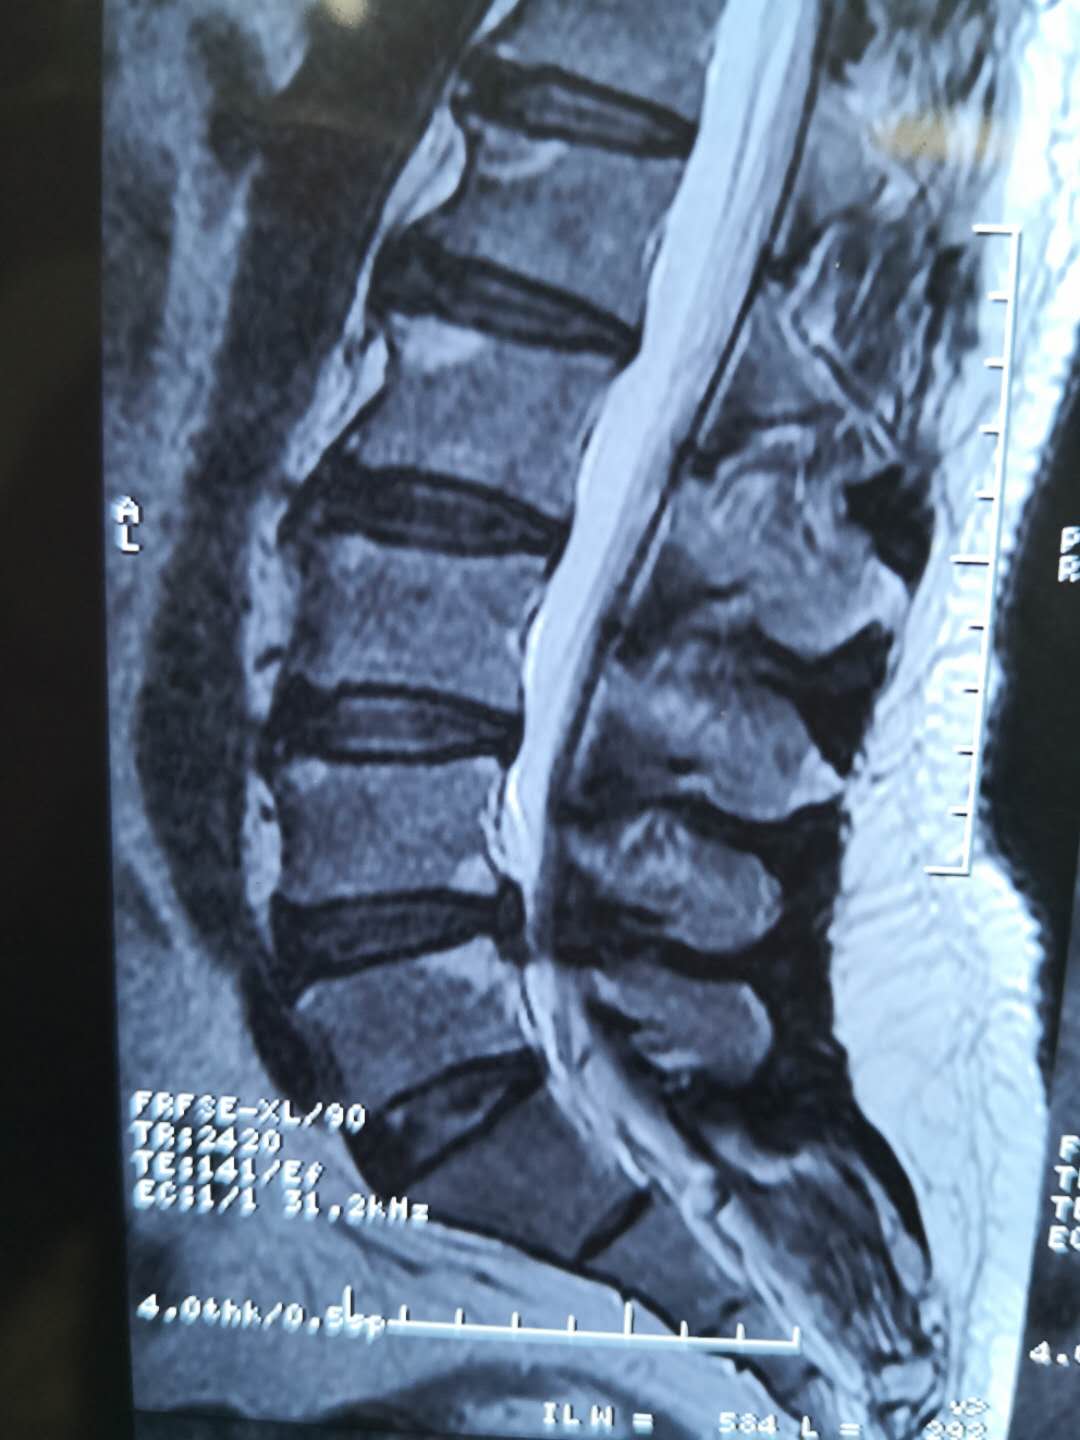

9月25日這天衢州骨傷科醫院習超杰院長門診哀痛連連,了解后才知道,52歲先生10年以來腰背部反復疼痛,彎腰和做完農活后更加脹痛,卻一直未去醫院就診。1月前林先生突然腰背部疼痛加重和左側臀部疼痛,休息一下會稍微好點,這次的腰背部疼痛加重引起了林先生的重視,在當地多家醫院治療,給予林先生中藥調養,腰部疼痛也的確有好轉。9月25日林先生的腰部酸脹痛比治療前更嚴重,已經影響正常生活,經打聽隨后到衢州骨傷科醫院就診。

林先生就診時對習超杰院長說:習院啊,你快幫我治治吧,我都快痛死了,哎喲~哎喲~痛啊。習超杰院長拿到檢查報告問:以前沒有高血壓、糖尿病、冠心病??;林先生回答說沒有,除了腰比較痛以外,沒有其他的??;習院長叫林先生躺上治療床進行檢查,結果為:棘突間及椎旁壓痛明顯,左側臀部壓痛(-),左側直腿抬高試驗80°(+),加強試驗(+),右側直腿抬高試驗90° (+),左側4字試驗(+),挺腹試驗(-),雙側跟臀試驗(+),觸診雙下肢肌肉緊張度可,左側晦趾背伸肌力IV級,左側胭繩肌肌力減弱,雙跖屈力雙下肢膝腱、跟腱反射正常;道:根據你的檢查結果你有“腰椎間盤突出癥”,只是略微有點嚴重,本來可以非手術治療,現在得住院手術,不過你也不用太愁心,治得好的。

林建新,男,52歲,腰痛10余年加重伴左下左下肢脹痛麻木1月?;颊?0年前出現腰痛,勞累加重休息緩解,反復發作,曾會診于當地多家醫院,1月前加重伴左下肢脹痛麻木,嚴重影響生活,在當地針灸理療無好轉來我院就診,.jpg

為迅速緩解患者癥狀,根據患者病情并結合影像學診斷,習超杰院長、非手術治療毛珺珺主任為患者制定了目前醫院最新微創手術方案UBE技術下經皮穿刺頸腰椎間盤切除術”。并為林先生家屬說明手術情況后,92620:00習超杰院長、非手術治療毛珺珺主任團隊的共同努力下,在透視下將UBE內鏡放入到腰椎間盤脫出部位,使用UBE專用器械靶精確定位,將神經根和硬膜囊牽向內側并保護起來后,精確摘除突出椎間盤,術中出血少約100ml,沒有出現其他異樣,23:30林先生手術非常成功,術后僅留下21厘米小切口,麻醉過后也并無異常。